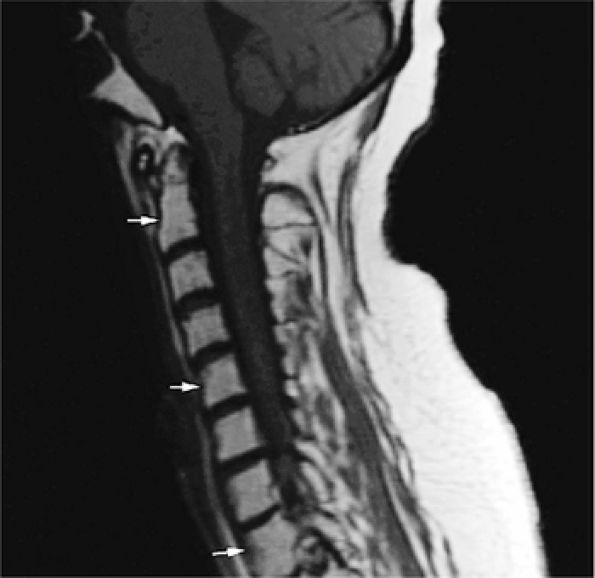

![]() |

FIGURE 13.37 ● Fatty marrow infiltration following radiation therapy for non-Hodgkin lymphoma. Sagittal T1-weighted image of the cervical spine shows diffuse bright-signal vertebral bodies (arrows).